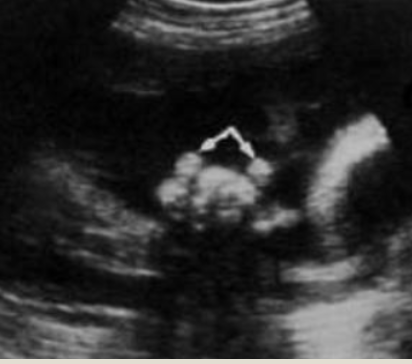

spinal defects are indicated by?

asymmetry of the ossification centers

splaying of the posterior centers

a break in the overlying skin

which scan plane is most diagnostic?

transverse plane